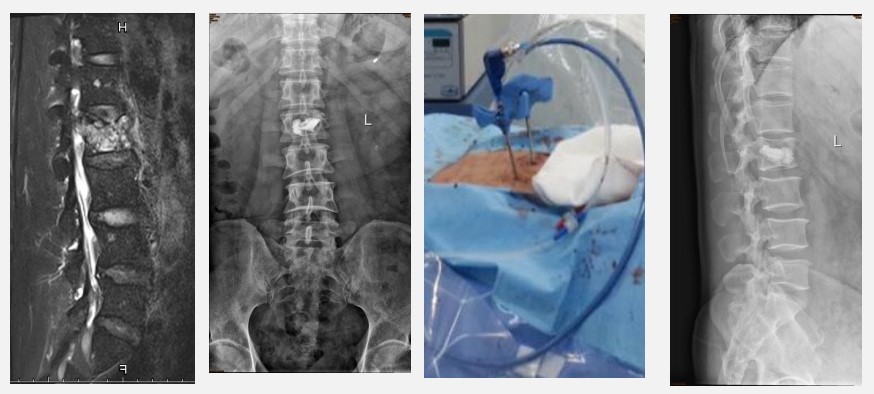

3.当体内癌细胞出现锥体转移,并出现神经功能受损、脊椎不稳定等情况,可采取微创肿瘤灭活,骨水泥填充的方法,迅速缓解患者疼痛。